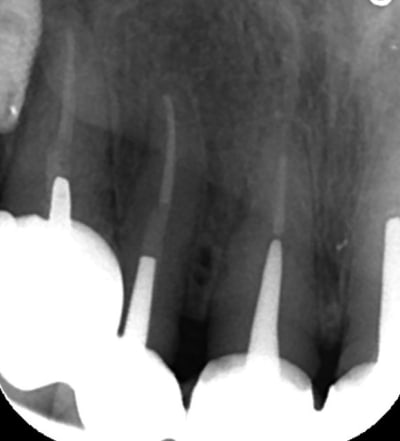

Mon petit cas galère du moment...

Péri-implantite 14 et 26.

25 explosée.

Infection apicale 13, 12, 33 (chaque 2 mois sous antibio depuis pas mal de temps...)

Et gros bouchon de fugy de 2 à 3 mm au fond du logement de l'inlay core, que j'ai dû traverser à la fraise diamantée pour pouvoir retraiter la 13 et la 12... :-)

Des pano comme ça, j'en vois tous les deux jours, avec des lésions apicales un peu partout.

Là, le dentiste (retraité depuis peu) a tout couronné, mis deux implants en plus pour rien, puis un stellite avec attachement (avec les implants en dessous qui ne servaient à rien...).

28/10/2014 à 23h43

jolies les endo! quel est le système que tu utilises ? gutta chaude ? système ??